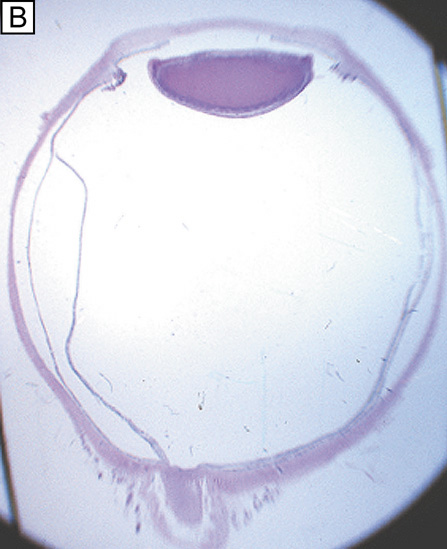

The endothelium of the infant cornea is composed of a single layer of approximately 500,000 neural crest-derived cells, each measuring around 5 μm in thickness by 20 μm in diameter and cover a surface area of 250 μm2.58,85 The cells lie on the posterior surface of the cornea and form an irregular polygonal mosaic. The tangential appearance of each corneal endothelial cell is uniquely irregular, usually uniform in size to one another, and typically six-sided (i.e., hexagons). They abut one another in an interdigitating fashion with 20 nm wide intercellular space between each other. The intercellular space is known to contain discontinuous apical tight junctions (macula occludens) and lateral gap junctions, thereby forming an incomplete barrier to diffusion of small molecules. As corneal endothelial cells have numerous cytoplasmic organelles, particularly mitochondrial organelles, they have been inferred to have the second highest aerobic metabolic rate of cells in the eye next to retinal photoreceptors.58

At birth, the central endothelial cell density of the cornea is around 5,000 cells/mm2.85 Because the corneal endothelium has very limited regenerative capabilities, there is a well-documented decline in central endothelial cell density with age that typical involves two phases: a rapid and a slow component.85,86 Due to corneal growth and age-related, or developmental, selective cell death, during the fast component, the central endothelial cell density decreases exponentially to about 3,500 cells/mm2 by age 5 years and 3,000 cells/mm2 by age 20 years.86 Thereafter, a slow component occurs where central endothelial cell density decreases to a linear steady rate of 0.6% per year, resulting in cell counts around 2,500 cell/mm2 in senescence (Fig. 20).85.86 Because endothelium maintains its continuity by migration and expansion of surviving cells, it is not surprising that the percentage of hexagonal cells decreases (pleomorphism) and the coefficient of variation of cell area increases (polymegathism) with age.86

It is important when reviewing this information to realize that these are average central corneal endothelial cell measurements from predominantly Caucasian U.S. populations, as racial and geographic differences can exist. Also, understand that this data applies only to central corneal endothelial measurements because recent work has shown that higher cell densities can typically be found in more peripheral aspects of the cornea (Fig. 21).87 Therefore, based on these studies, it appears that central corneal endothelial cell numbers decrease on average about 50% from birth to death in normal subjects. Because corneal decompensation typically does not occur until central values reach around 500 cells/mm2, there appears to be plenty of cellular reserve potential remaining after an average human life span.86 Estimates suggest that healthy, normal human corneal endothelium could maintain corneal clarity up to a minimum of 215 years of life, if humans lived that long.85